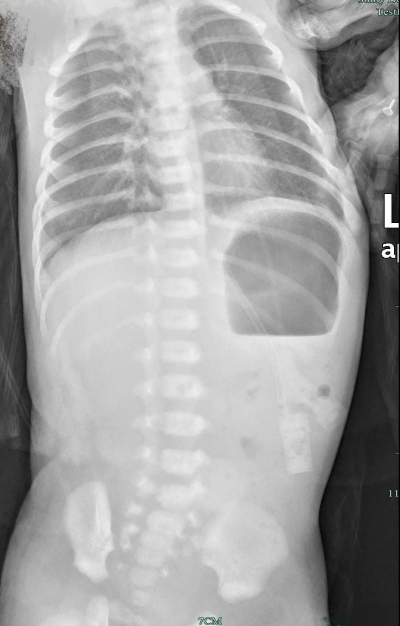

最近,出生才3天的闪闪(化名)因为黄疸转至杭州市儿童医院新生儿科。住院当天,闪闪呕吐了一次,呕吐物呈草绿色,似胆汁和胎粪。周素芽判断闪闪可能存在消化道问题,当即安排腹部立位拍片,结果显示闪闪的下腹部只见到非常少量的气体!

(图片:闪闪的腹部立位片,正常新生儿腹部应有生理积气)

追问病史,家长表示闪闪出生最初两天就有呕吐,吐得不多,都是透明泡沫样的液体。由于妈妈奶水少,孩子喂奶量也少,后来就没发现有呕吐现象,而且闪闪出生后胎便解了四五次,量也不少,因此排除了先天性肠闭锁的可能。

那是怎么回事?与医院外科专家共同会诊后,闪闪被安排了肠系膜血管B超检查及消化道造影检查,最终考虑为先天性肠旋转不良,这也是消化道畸形的一种。如果把肠道比喻为水管,闪闪肠道的中间部位则是扭了一个540度的“结”,造成了肠梗阻,所以喝下的奶无法顺利通过肠道消化吸收,只能重新吐出来。由于梗阻的位置偏低,吐出来的是胆汁样和墨绿色粪汁样的液体。